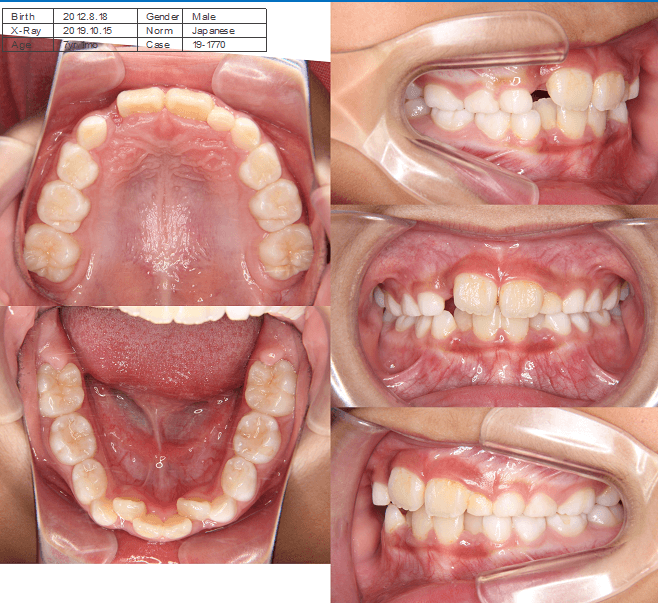

上歯前突+叢生症例 成長期

主訴 | 口元の突出感と歯並びが気になり、将来的な咬合状態を整える目的で来院された患者様です。 |

---|---|

診断結果 | 11歳1か月の女性。骨格的には日本人標準に近く、歯性の上顎前突および叢生が認められました。上下顎ともに歯列のスペース不足があり、永久歯の萌出や歯列の整列に支障をきたす可能性があると診断されました。 |

治療内容 |

|

治療後の経過 | 動的治療終了後は、上下顎の歯列が整い、口元の突出感と叢生が改善されました。審美的・機能的なバランスが取れた状態となり、現在は取り外し式リテーナーを使用し、保定期間に移行しています。 |

治療期間 | 動的治療期間:2年6か月 通院回数:25回 |

治療費用 | 720,000円 |